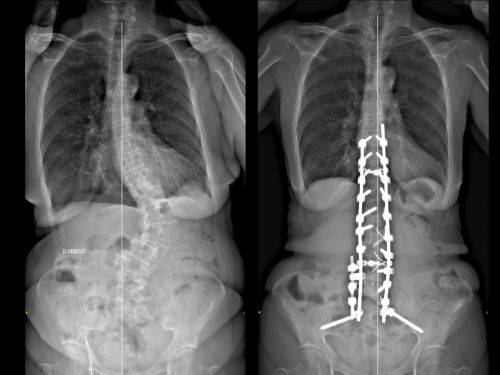

Une scoliose correspond à une déformation de la colonne vertébrale impliquant une déformation des vertèbres et des disques. Cette déformation est liée à la rotation de vertèbres. La rotation entraine une déformation dans les 3 plans de l’espace. La scoliose est une pathologie tridimensionnelle. Celle-ci s’apprécie d’abord cliniquement : se mesure par la gibbosité (en flexion du tronc, on mesure la différence entre les arcs costaux postérieurs). Cette gibbosité correspond à une déformation du dos en forme de « bosse ».

La radiographie de la colonne vertébrale nous apporte des informations complémentaires sur la scoliose, notamment avec l’angle de Cobb. Par définition, une courbure coronale de 10° ou plus (angle de Cobb) doit être présente pour diagnostiquer une scoliose. Lorsqu’une scoliose est diagnostiquée, un suivi régulier clinique et radiologique est primordial.

Les analyses radiologiques désormais largement accessibles apportent des informations déterminantes pour le diagnostic positif et différentiel : les radiographies, debout en charge, permettent de fournir des informations statiques et divers paramètres radiologiques. Ces paramètres importants sont reconnus comme des facteurs d’évaluation de l’état fonctionnel initial et de l’impact du traitement.

Pour ce type d’analyse, l’examen type EOS est une référence. Il correspond à une radiographie du rachis, de face et de profil, corps entier et permet de préciser l’équilibre global des patients dans le plan sagittal et le plan frontal. Un des paramètres importants pour l’évaluation d’une scoliose est l’angle de Cobb. Cet angle joue un rôle central. Ce paramètre permet de déterminer la gravité de la scoliose et permet également d’assurer son suivi. Ces données permettent d’avoir un suivi précis des patients afin d’ajuster la prise en charge en fonction de l’évolution. Associées aux paramètres fonctionnels, elles donnent des informations sur l’état structurel du patient, permettant une évaluation plus globale de la maladie vertébrale.